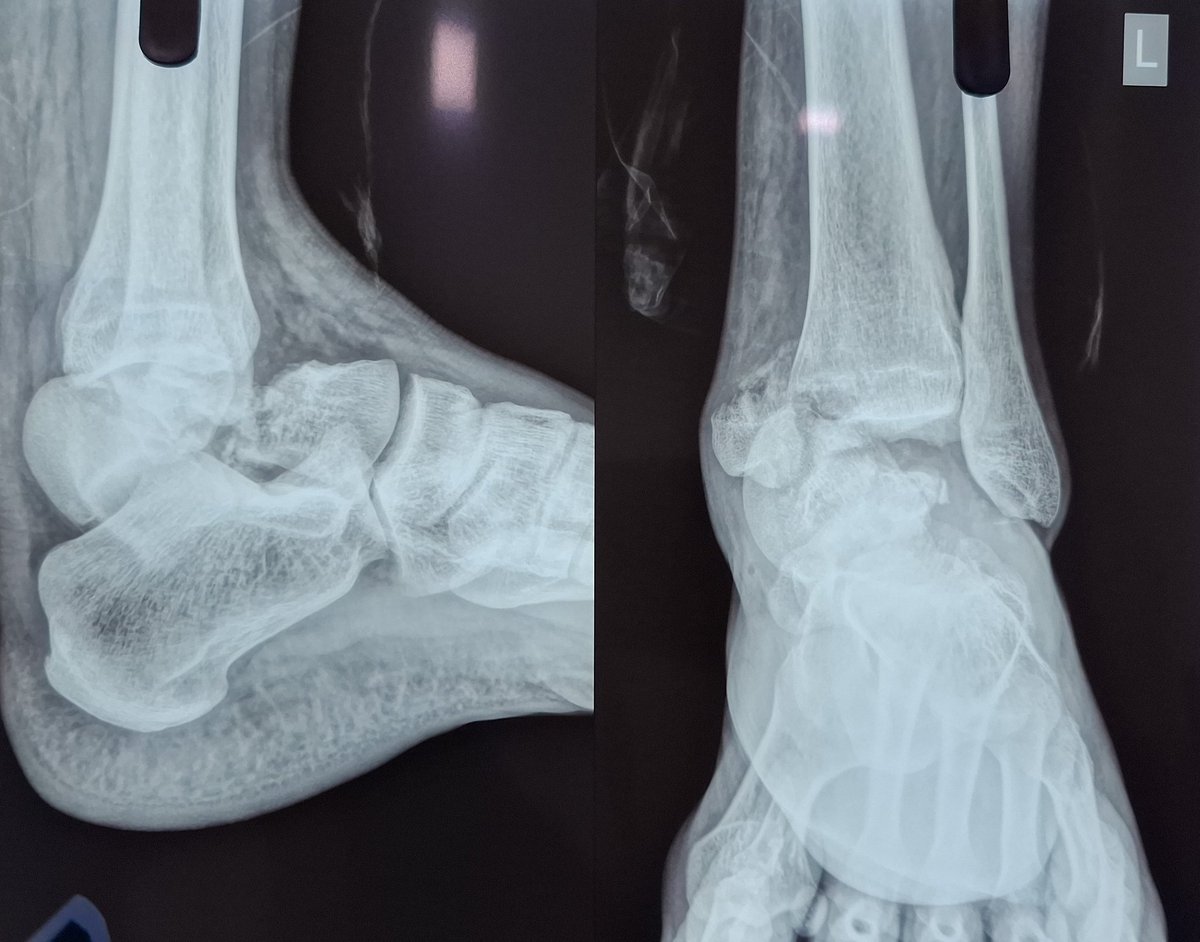

#orthotwittter @Drlyndonmason # talus Closed injury Body dislocated & locked PM side MM # Lateral comminution Not on medial side Dual approach Joint distraction using double bend Hintermann Pins in distal tibia & navicular keeping Foot in plantar flexed Valuable feedback🙏🙋